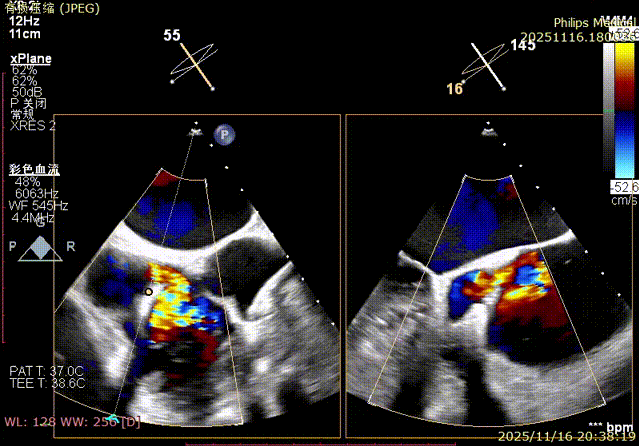

Echocardiographic Assessment: Echocardiography revealed left atrial enlargement. The left atrial appendage (LAA) orifice was 32mm with no thrombus inside. Tricuspid regurgitation was extreme (average vena contracta 18mm). Regurgitant jets were located at the anterior-septal, central, and posterior-septal commissures, with a central gap measuring approximately 13x5.9mm. The annulus was mildly dilated (average diameter 43mm). The tricuspid leaflets showed thickening and degenerative changes.

Immediate intraoperative echocardiographic verification showed that the tricuspid regurgitation area was significantly reduced from a preoperative grade of 5+(pre-op) to 2+(post-op), downgrading the severity from extreme to mild-moderate.

1.Baseline assessment of regurgitation severity.

Comparison of TR regurgitation severity: reduced from 5+ to 2+

preoperative

postoperative

- TR Severity Comparison: Reduced from 5+ to 2+.